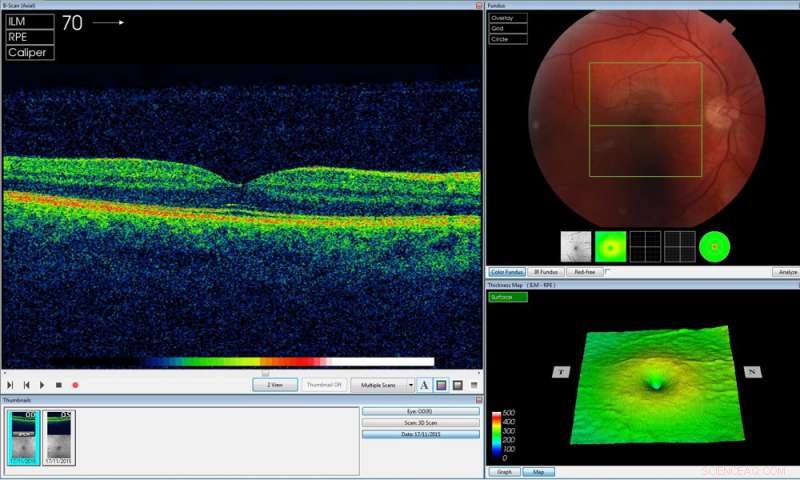

Credit: University College London

Using two types of neural network – mathematical systems for identifying patterns in images or data – the AI system quickly learnt to identify ten features of eye disease from highly complex optical coherence tomography (OCT) scans. The system was then able to recommend a referral decision based on the most urgent conditions detected.

The AI has been developed with two unique features which maximise its potential use in eye care. Firstly, the system can provide information that helps explain to eye care professionals how it arrives at its recommendations. This information includes visuals of the features of eye disease it has identified on the OCT scan and the level of confidence the system has in its recommendations, in the form of a percentage. This functionality is crucial in helping clinicians scrutinise the technology's recommendations and check its accuracy before deciding the type of care and treatment a patient receives.